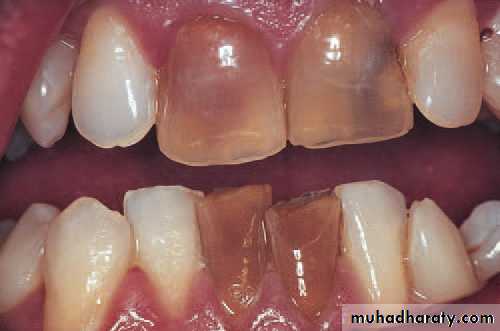

Non-vital incisor teeth, in this case as a result of trauma.Haemorrhage and products of autolysis of the pulp discolour the dentine and darken the teeth.